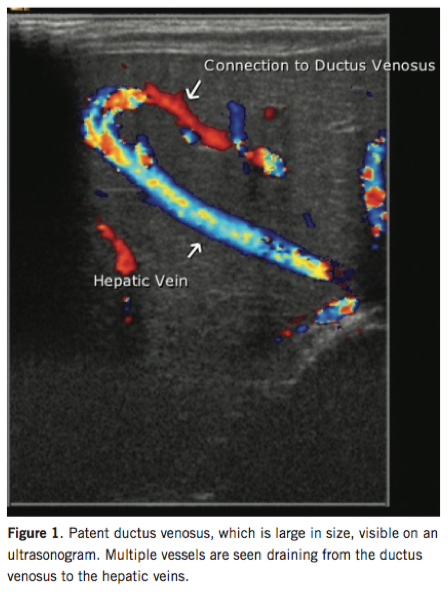

Michael Rogers, DO; Kyle Brady, DO

A 3-day old boy, born at 38 weeks of gestation and weighing 2.7 kg at birth, presented for his initial newborn visit after an uneventful stay in the nursery.